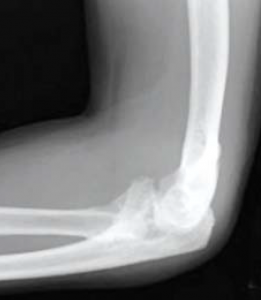

Bei zusätzlichen Knochenbrüchen im Rahmen einer Luxation müssen diese mitbehandelt werden, da das Ellenbogengelenk vor allem knöchern geführt wird. Je nach Ausprägung müssen offene Osteosyntheseverfahren mit Schrauben und Platten an der Elle (Ulna), Speiche (Radius) und dem unteren Oberarm (distaler Humerus) vorgenommen werden. Eine besondere Bedeutung kommt dabei dem Processus coronoideus zu, der die Stabilität in

Streckung unterstützt. Auch das Radiusköpfchen kann so erheblich verletzt sein, dass eine Rekonstruktion nicht möglich ist und dann dieses entfernt werden muss. Die Entscheidung, dann eine Radiusköpfchenprothese zu implantieren, hängt von der verbleibenden Instabilität ab. Liegt eine starke mediale Instabilität vor, kann als sekundärer Stabilisator eine solche Prothese implantiert werden.